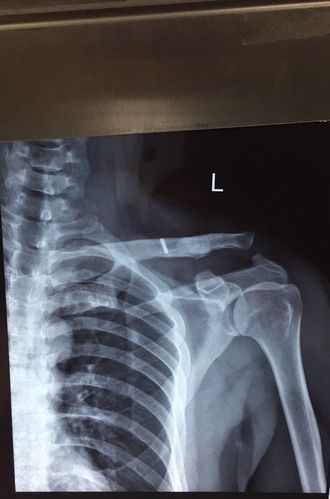

肩锁关节一度脱位图片

肩锁关节一度脱位图片,肩锁关节半脱位图片

肩锁关节脱位

肩锁关节半脱位图片

肩锁关节二级脱位图片

三度肩锁骨脱位图片

肩锁关节正常图片